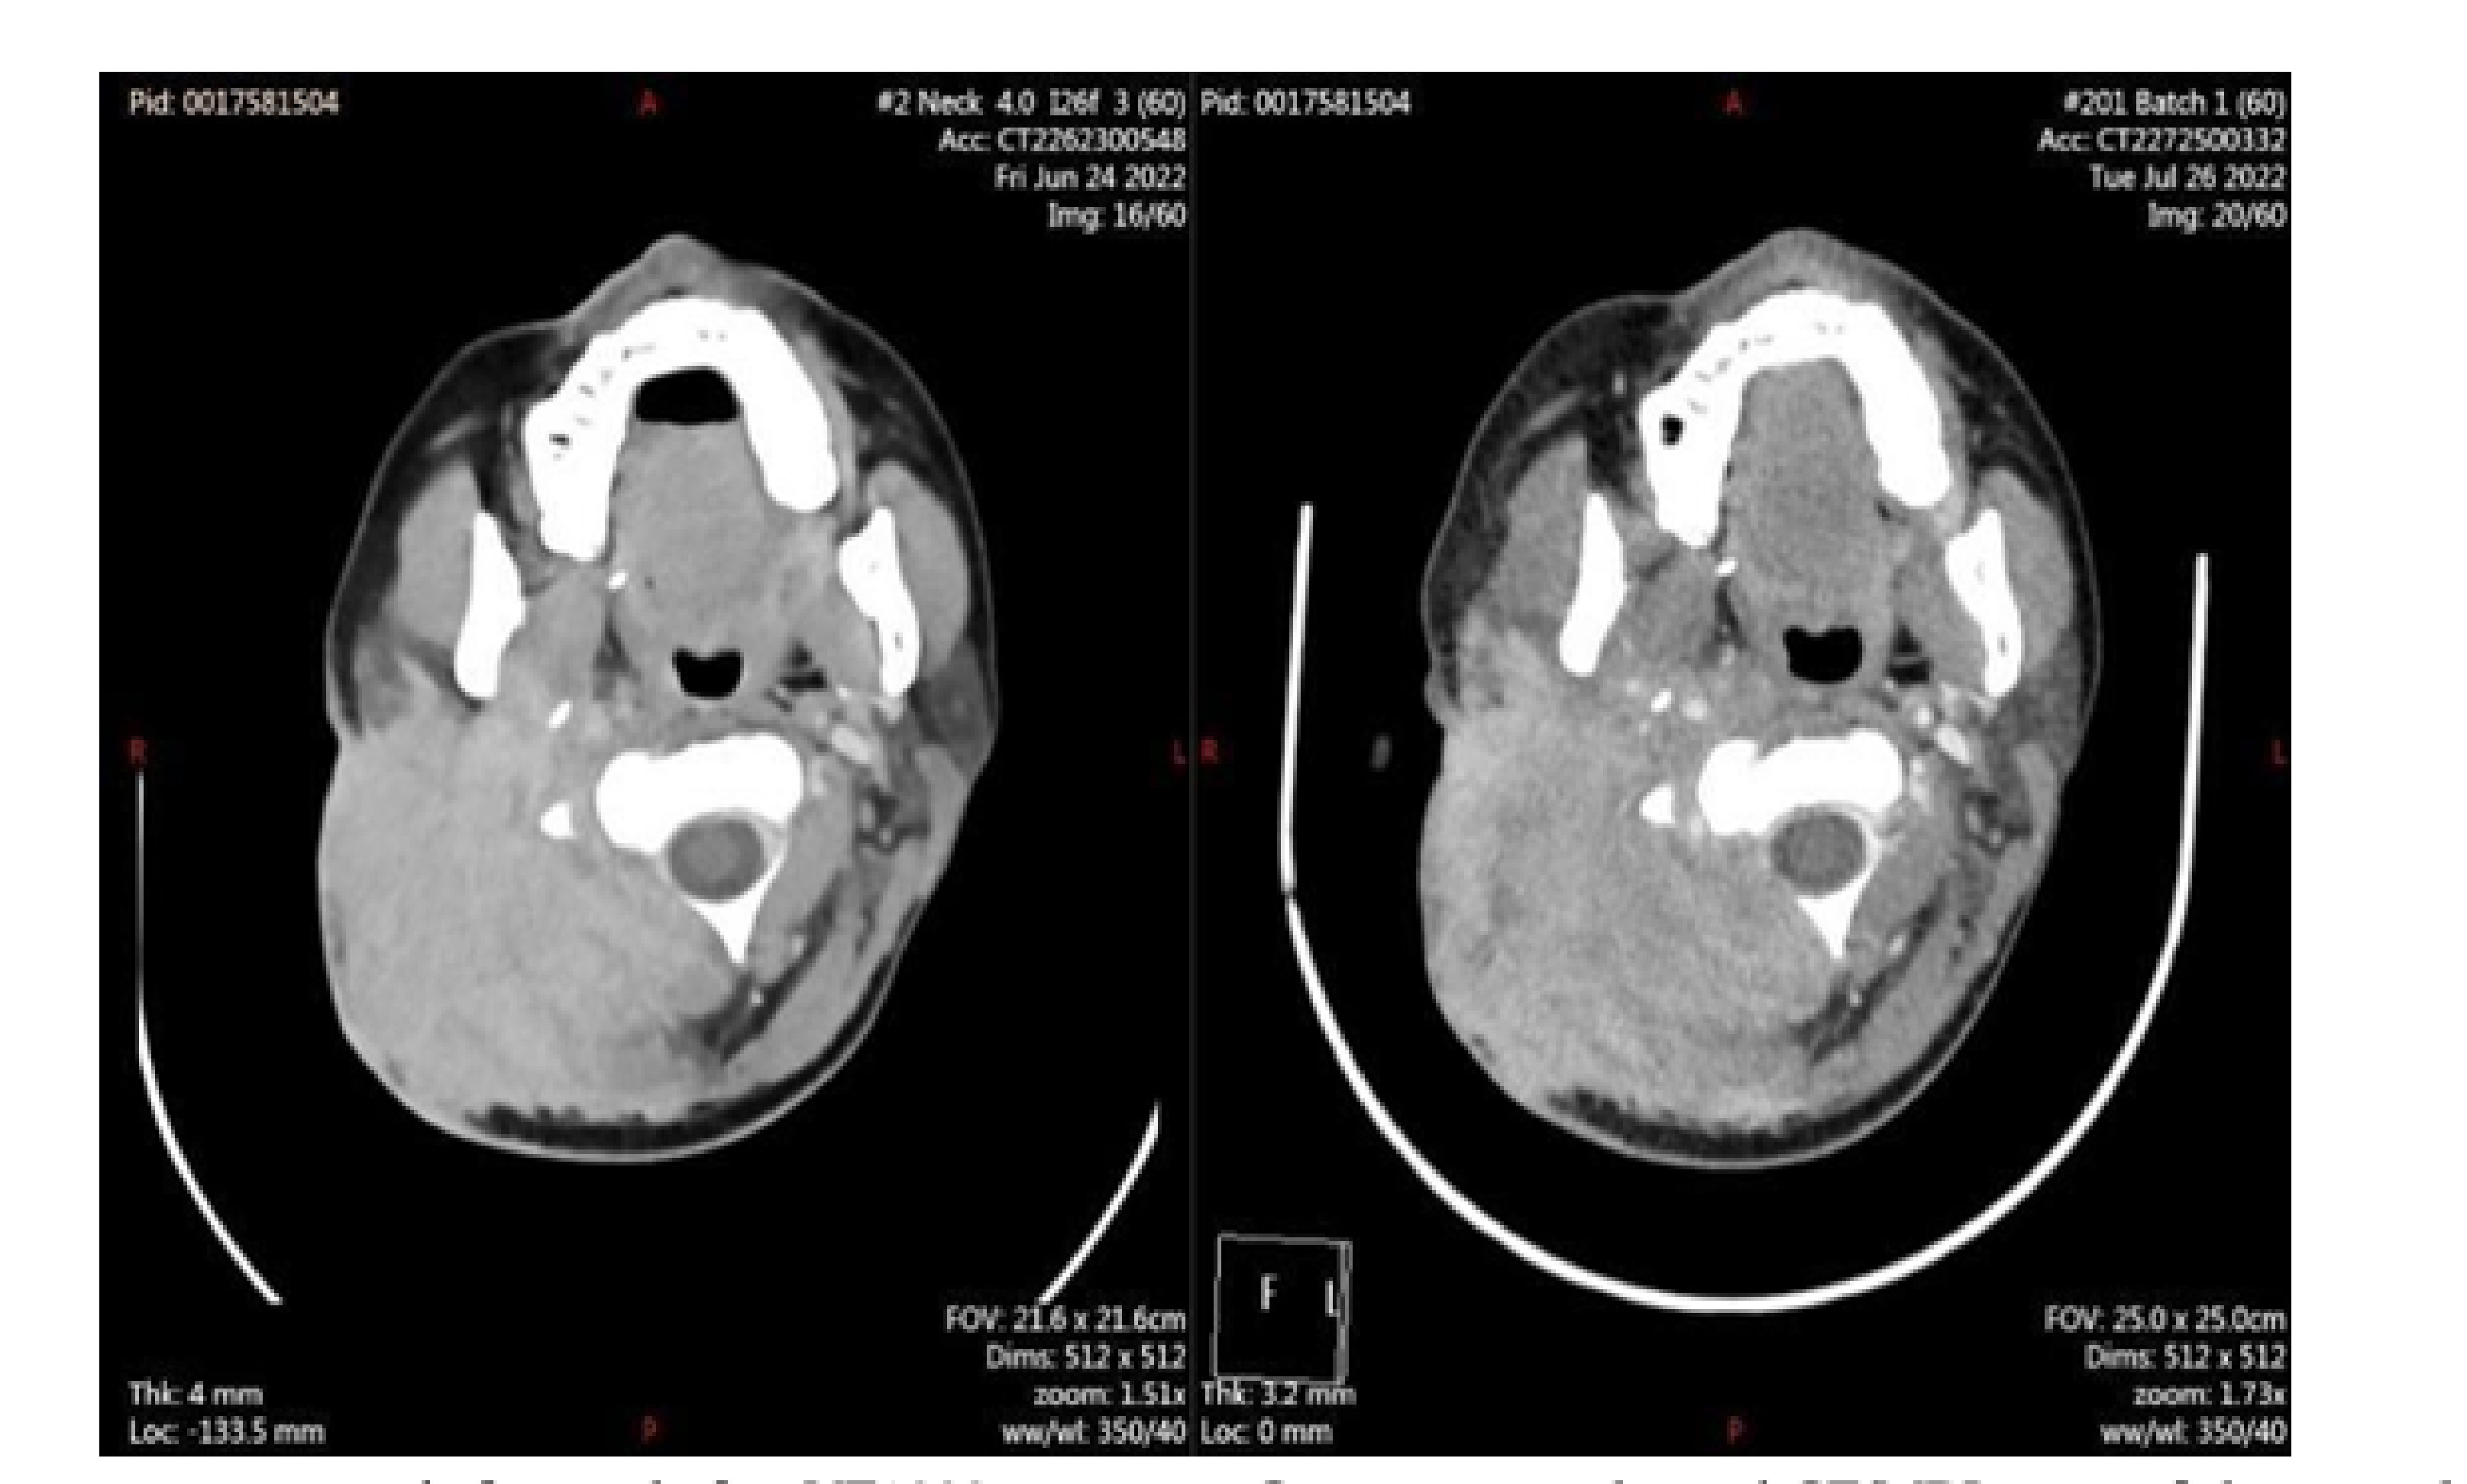

2026年3月20日,鹏博(海南)硼中子医院顺利完成了第2例硼中子俘获治疗(BNCT)患者的临床治疗。继首例舌癌患者治疗后,该院在头颈部恶性肿瘤BNCT临床治疗领域再添新案例。